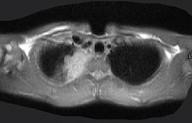

问题 男,28岁,咳嗽,咯血,消瘦盗汗1个月余,影像学检查如图。最可能的诊断为 ( )

选项 A.类风湿肺炎 B.右上肺周围型肺癌 C.右上肺浸润型肺结核 D.右上肺炎性假瘤 E.右上肺曲真菌感染

答案 C